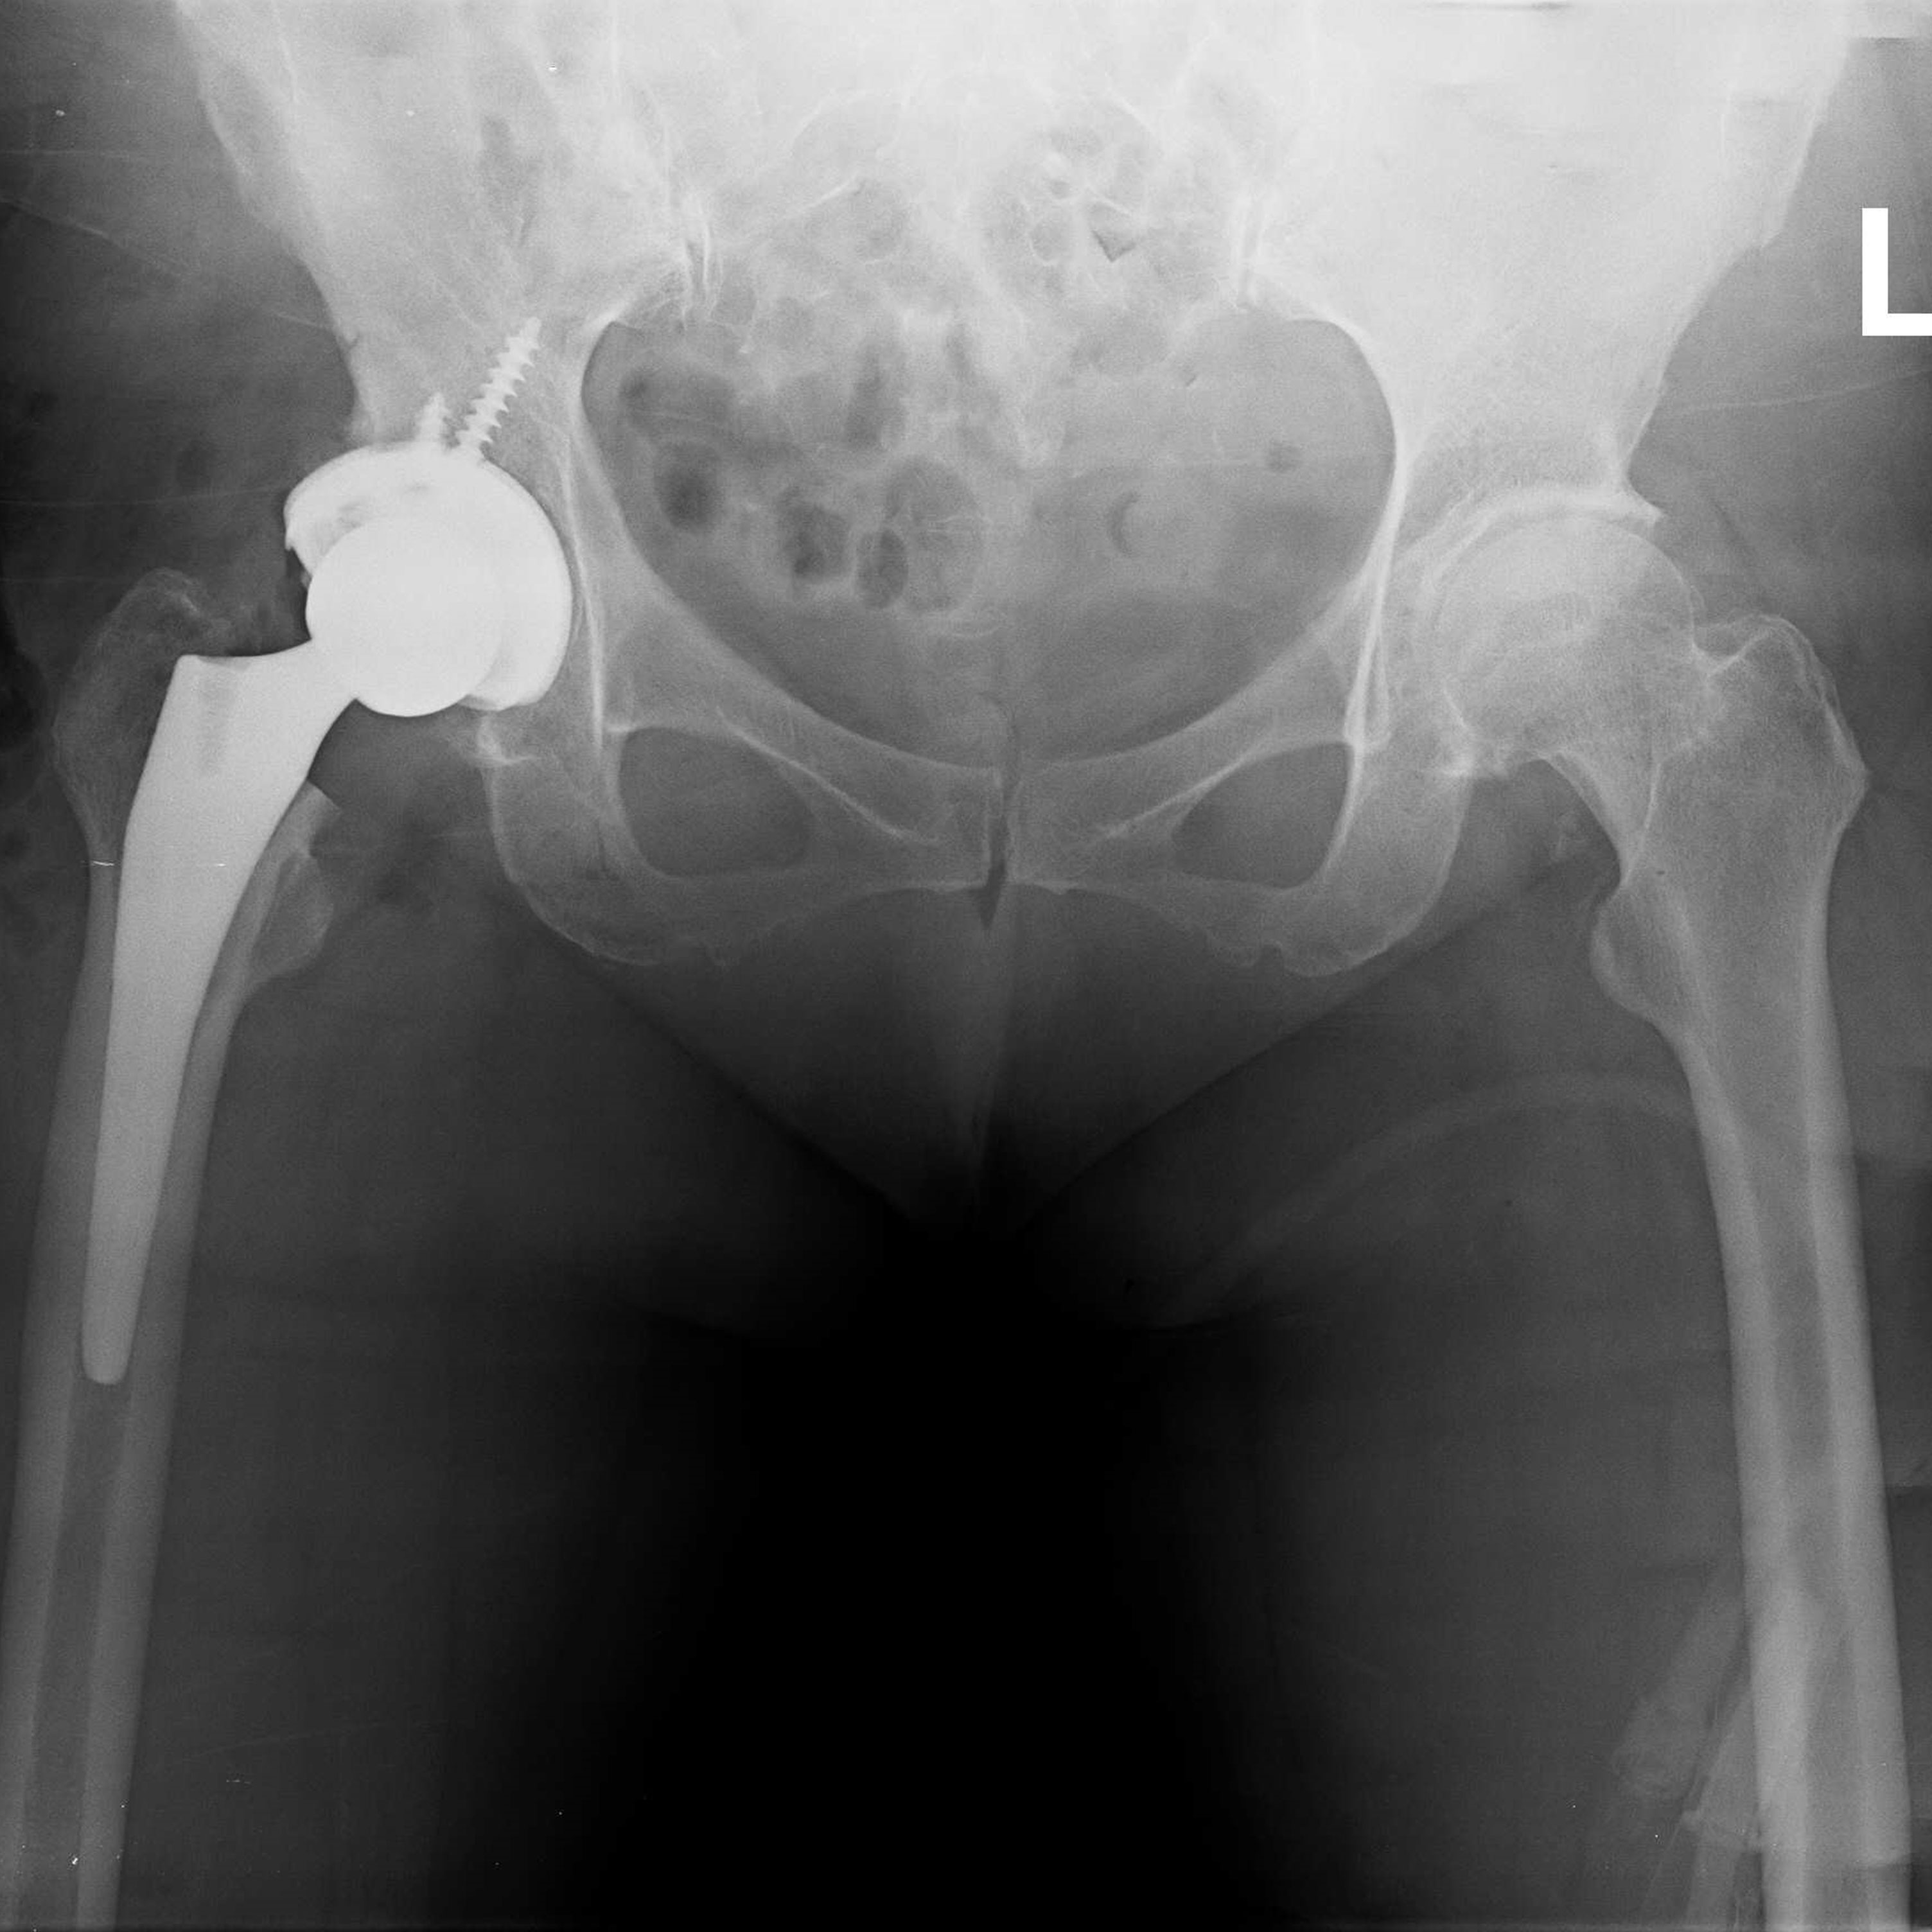

機器手臂手術 首頁 案例分享 髖關節手術 機器手臂手術 72歲 楊女士 退化性關節炎 術前 術後 60歲 彭先生骨股頭壞死 術前 術後 53歲 王女士退化性關節炎(DDH先天發育不全 CROWE TYPE 2) 術前 術後 83歲林女士退化性關節炎 術前 術後 83歲林女士退化性關節炎 術前 術後 楊女士 70歲 術前 術後 蔡女士 60歲 術前 術後